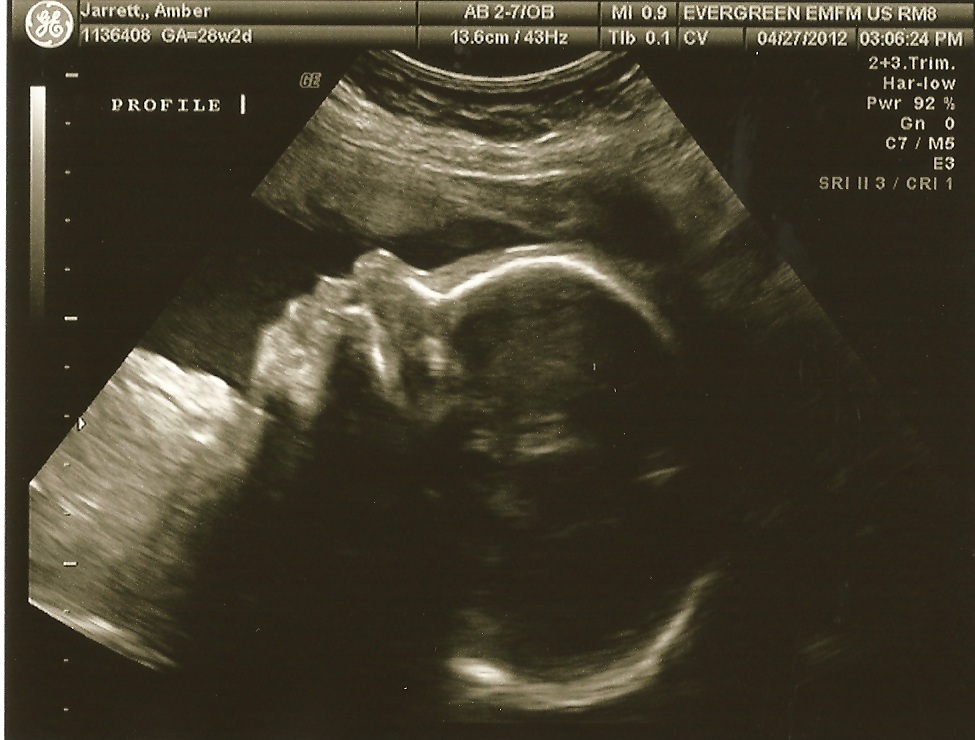

Baby head profile.